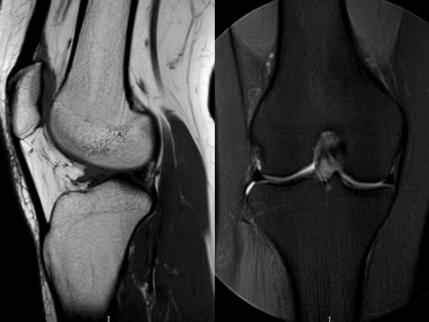

1. “咯吱響”+“卡頓感”——半月板的“碎玻璃警報”

場景:下蹲時膝蓋“咯噔”彈響,起身像被“卡住”

MRI偵查:精準(zhǔn)捕捉半月板撕裂或變性(半月板內(nèi)高信號),避免拖成“關(guān)節(jié)交鎖”

(半月板撕裂)